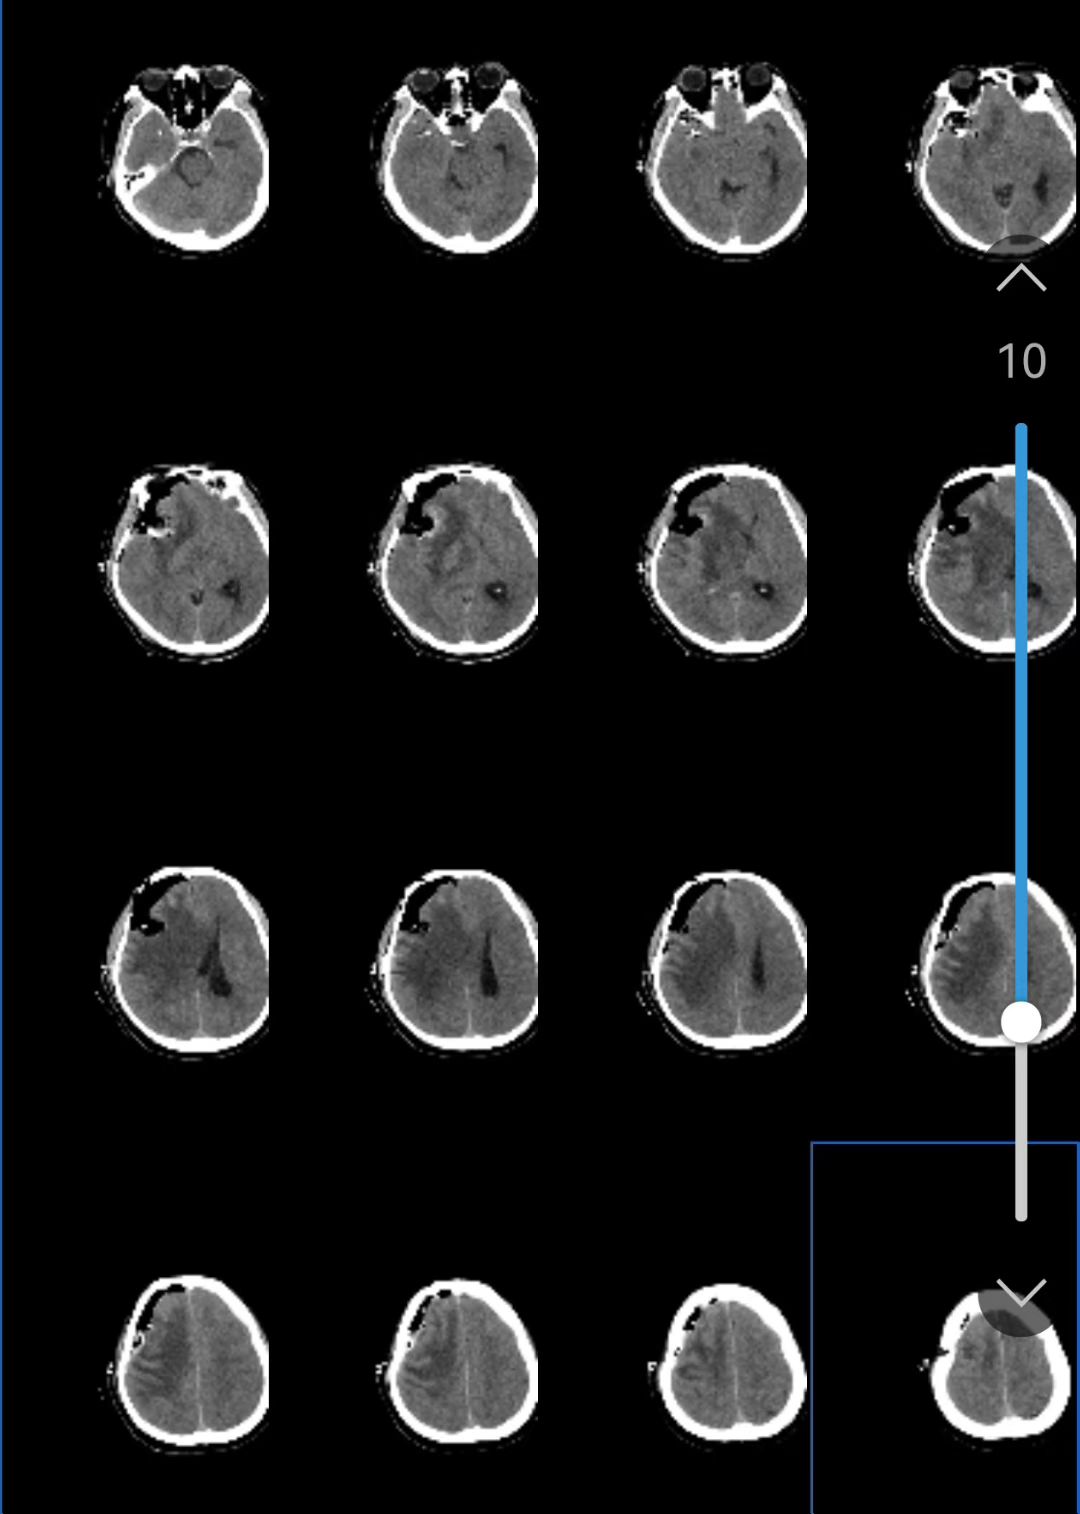

得益于术前栓塞取得了显著效果,手术过程中出血极少,手术视野清晰,医生们成功为佟先生完成“脑膜瘤切除+动脉瘤夹闭”联合手术。术后,佟先生神志清醒、四肢活动自如,恢复情况良好。

术后复查头部CT